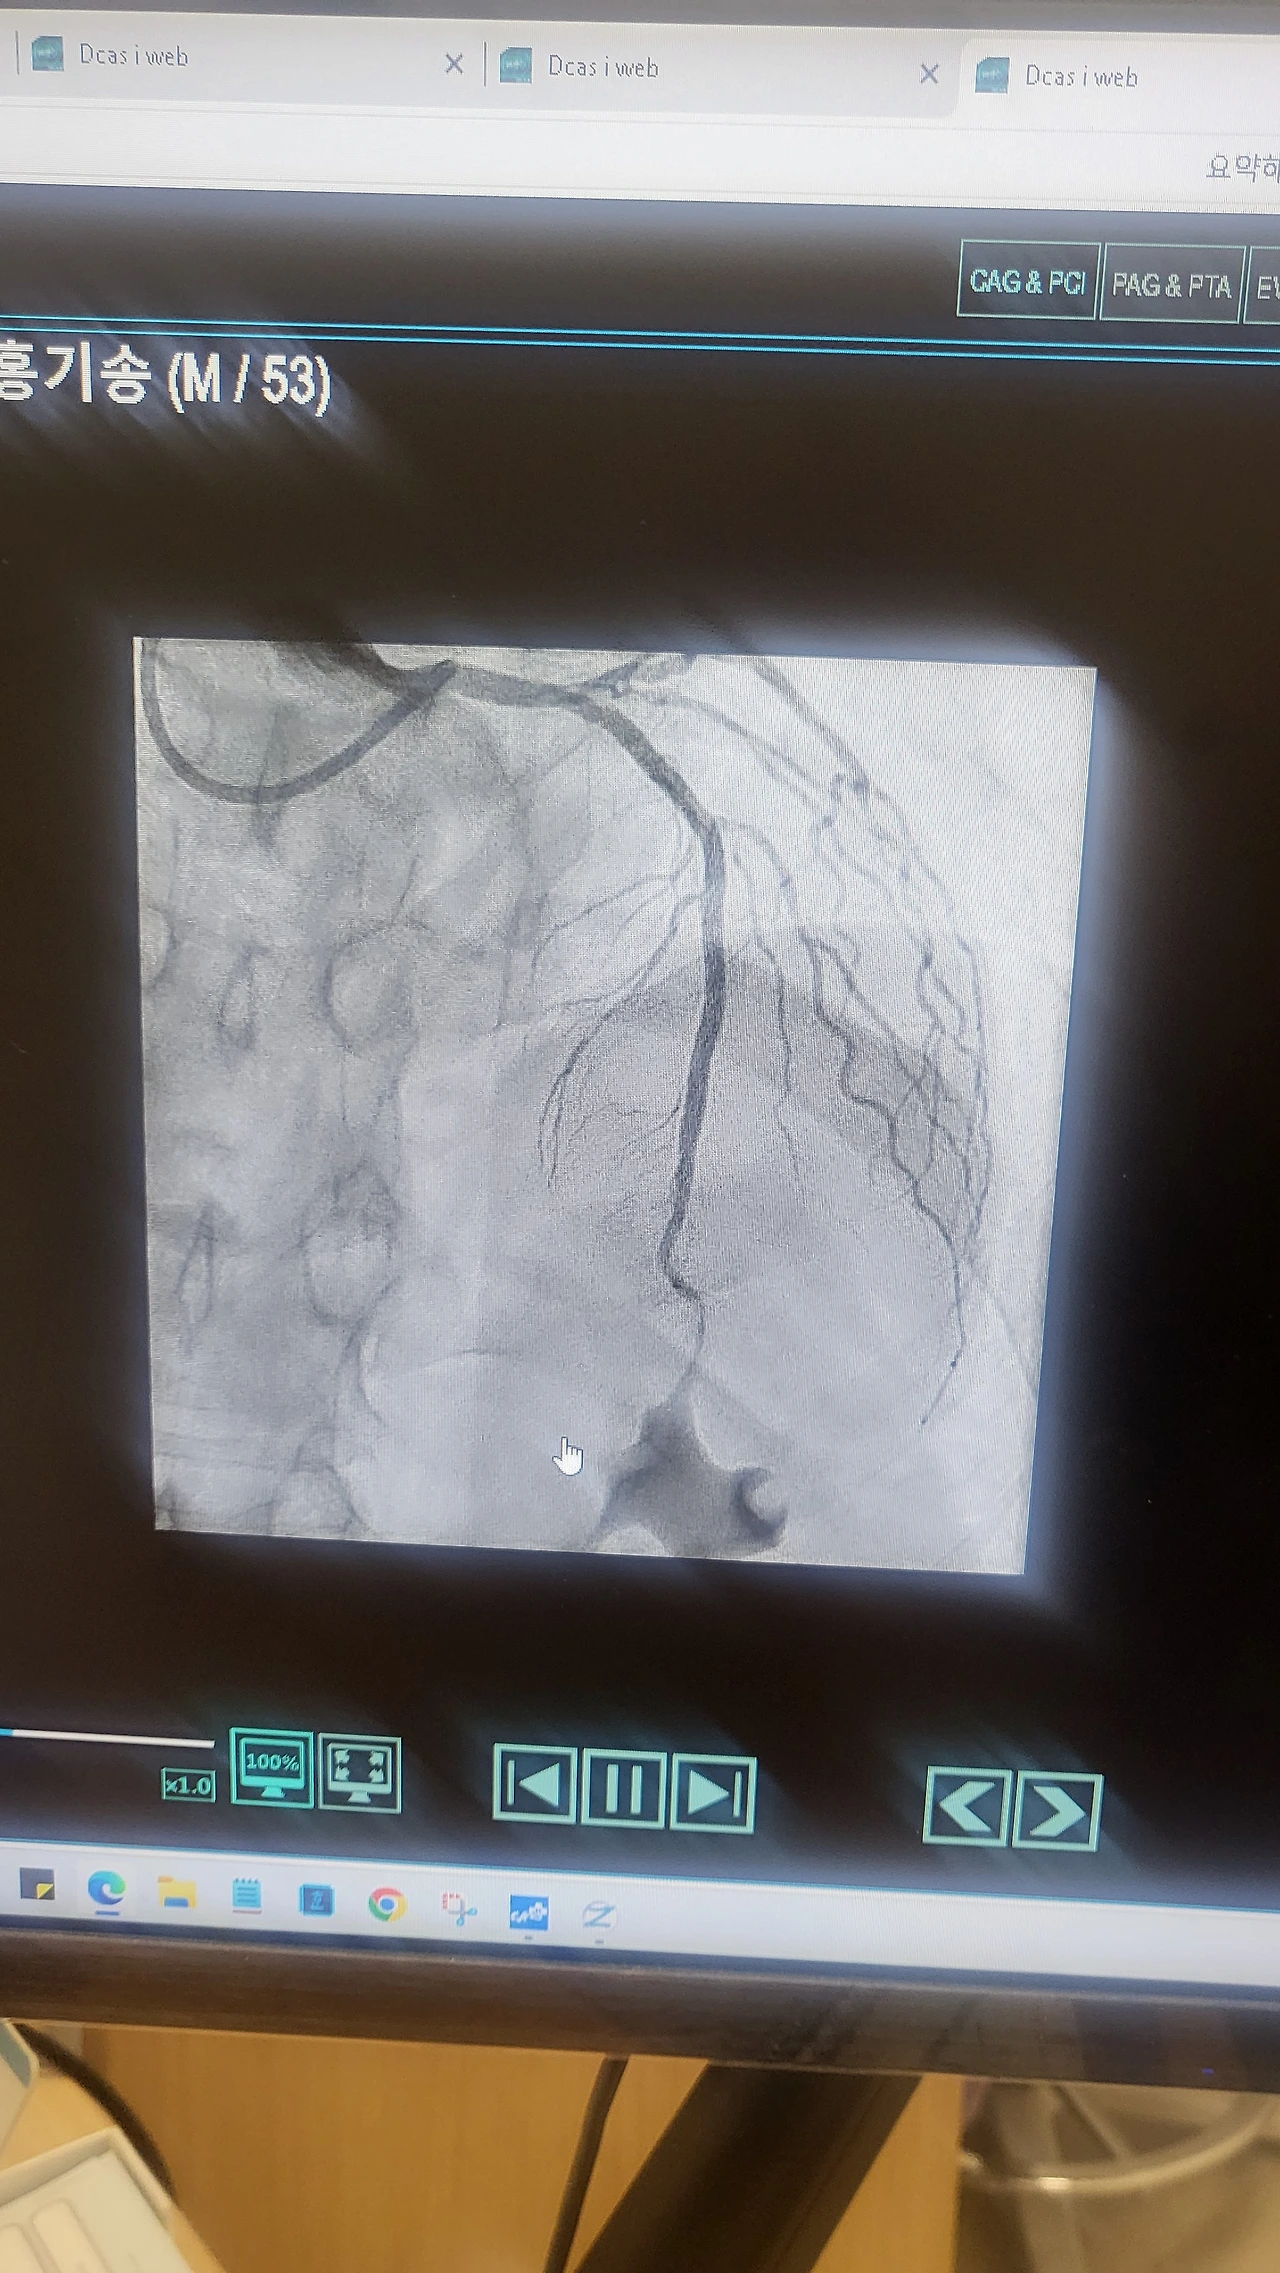

가슴 위로는 정사각형의 CT기계가 심장으로 흐르는 혈관들을 계속 찍고 있었다. 누워있는 침대 옆으로 커다란 모니터가 심장 속 혈류의 흐름을 사진 찍듯이 선명하게 보여주고 있었다. 조영제가 들어갈 때 막힌 곳과 좁아진 곳의 위치가 정확히 드러났다. 마치 자동차 안에서 보는 내비게이션처럼, 얽혀있는 심혈관들의 혈류가 강물 흐르듯 흐르고 있었다.

난 옆눈길로 모니터에 흐르고 있는 내 심장을 유심히 쳐다보았다.

"저게 나는구나 살아 있구나 저게 막혔다면 죽는 거구나 "

나의 심장은 뛰고 있었고 그곳에 여러 개의 와이어가 들어가 혈전을 뚫고 있는 상태였다. 그렇게 두 시간이 넘어가고 있었다. 생각해 보면 상반신을 드러낸 체, 정신은 말짱히 깨어있는 상태에서, 스탠트삽입 시술을 받는다는 게 쉽지만은 않았다.